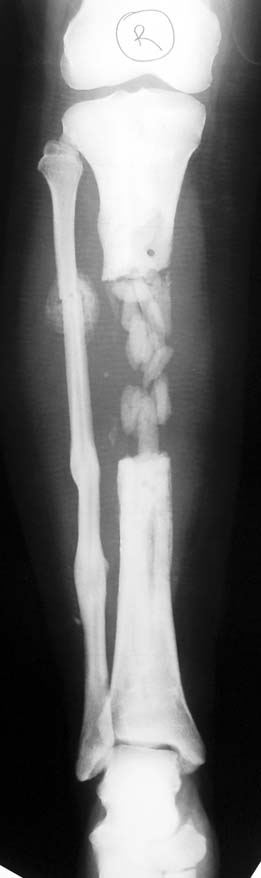

Kronik osteomiyelit, kemik ve yumuşak dokularda nekroza yol açar. Ölü kemik, patojen mikroorganizmalara ev sahipliği yapan bir nidus oluşturur. Konağın savunma sistemleri, mikroorganizmalarla baş etmek için sıklıkla optimal koşullarda değildir. Dolaşım bozukluğu yüzünden enfeksiyon bölgesine antibiyotikler yeterince ulaşamaz. Bu nedenle ölü dokuların ortamdan tamamen uzaklaştırılması gerekir (radikal debridman).

Uygun radikal debridman tüm nekrotik kemik ve yumuşak dokuların çıkartılmasını gerektirir, ve sıklıkla uzuvda instabiliteye neden olur. Kalan kemik ve yumuşak doku defektinin bir şekilde fiksasyonu ve rekonstrüksiyonu gereklidir. İlizarov’un ortaya koyduğu distraksiyon osteogenezi yöntemi, kaynamanın elde edilmesi, deformitenin düzeltilmesi, bacak boy eşitsizliğinin giderilmesi ve segmental defektlerin rekonstrükte edilmesi için başarıyla kullanılmaktadır.